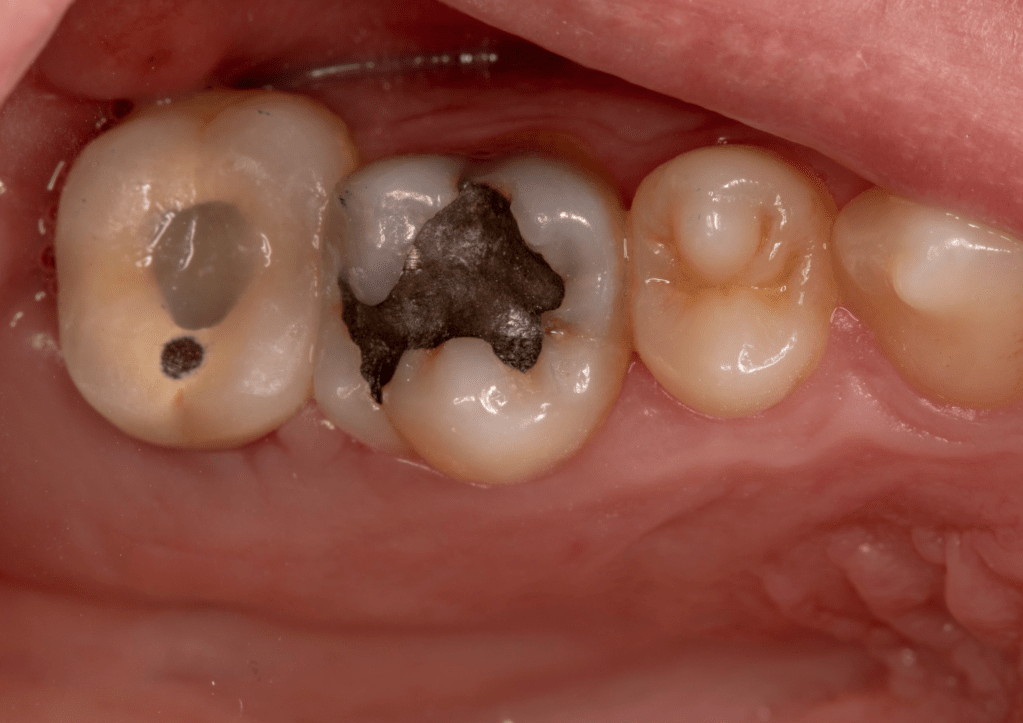

Fisura, remoción amalgama para explorar